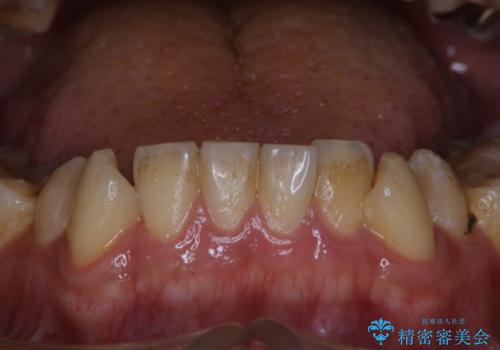

ワイヤー矯正終了時に装置除去と合わせてPMTC

担当医 歯科衛生士